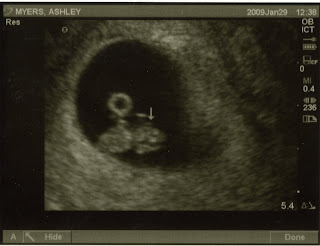

I had been feeling kinda weird I guess you could say. The girls (Bertha* and Martha*) were feeling tingly, like they were trying to tell me something... Plus, I kept getting dizzy (remember the Titan and the Omni theatre?) and that's not like me. So, one evening I made up an excuse to run to Target and grabbed the cheapest 2 pack of pregnancy tests I could find. When I got home I went straight to the bathroom and took one. Positive immediately. I got out of the bathroom and made dinner as if nothing was wrong. After everyone was asleep I took the second one- and it too was positive. All I can think of is that I am the lucky fart who got not one but two faulty tests. I mean Aunt Flow wasn't even due for 6 more days!! So, I immediately Google the brand of tests I bought and they are notorious for false positives. I knew it! I wasn't really with child... or was I? The next morning I ran to CVS and bought 5 more tests. I went home and walked straight to my bathroom and you guessed it- I took them all. My bathroom looked like a science lab. And, one by one they all came up positive. I guess you could say I'm a little dense, seeing as it took 7 tests for me to get the hint. It took me three whole days to tell my husband. I got my first positive on December 28th and held it in til New Year's Eve. He was a little shocked to put it mildly. I went back to Target within 30 minutes of telling him and bought the new edition of What to Expect When You're Expecting and a giant bottle of pre-natal vitamins. That next week my symptoms kicked into high gear. I must say being pregnant at 34 is nothing like being pregnant in your late teens and early twenties... I kept the news to myself as long as I could telling only a few people like my Relief Society prez (since I was suddenly sleeping ALOT and kept missing church) and my hairdresser, who along with my OB assured me it was safe to color my hair. I only recently told my kiddos, who were in total disbelief and asked if they were being Punk'd! I then slowly but surely started breaking the news to the whole world! I really wanted to surprise everyone and hope I was successful! So, there you have it- The Discovery. You know I am gonna get on here and blog some more about it, but I'll shut up for now. And, I promise to blog about something other than pregnancy all the time. Scout's Honor.